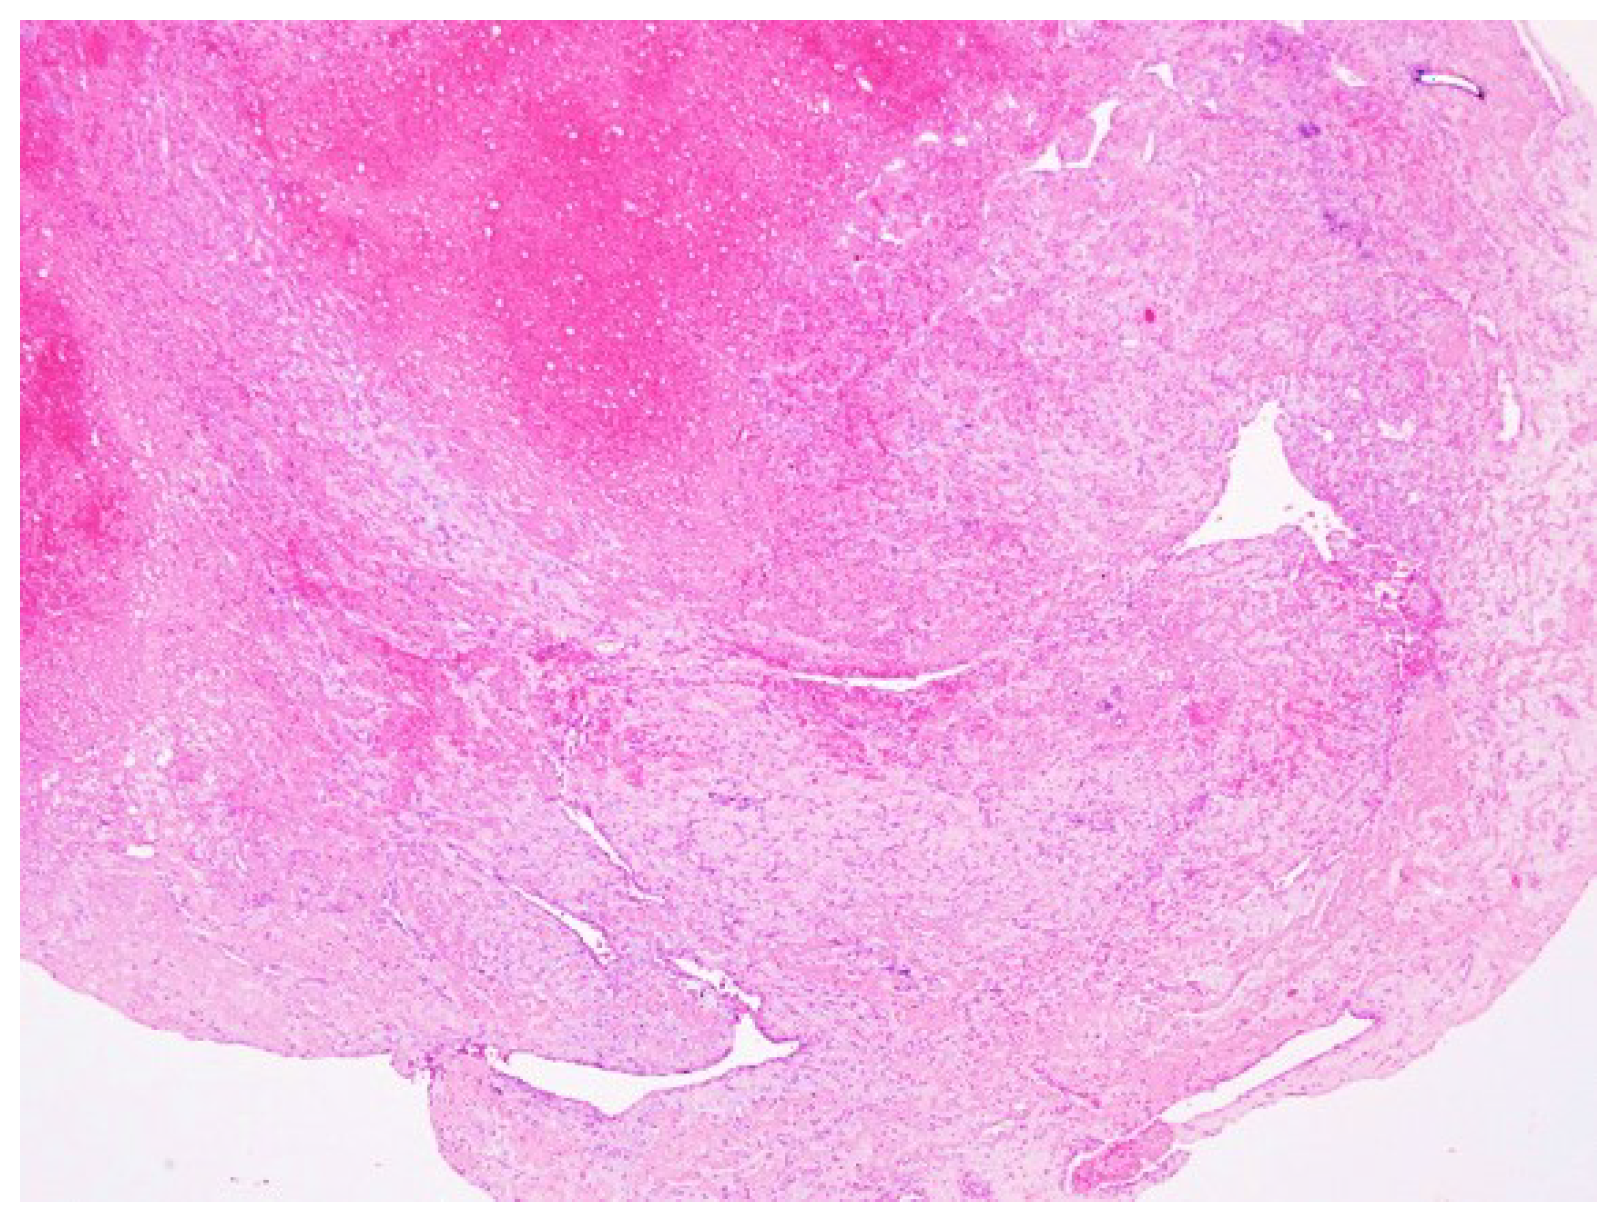

3. Results